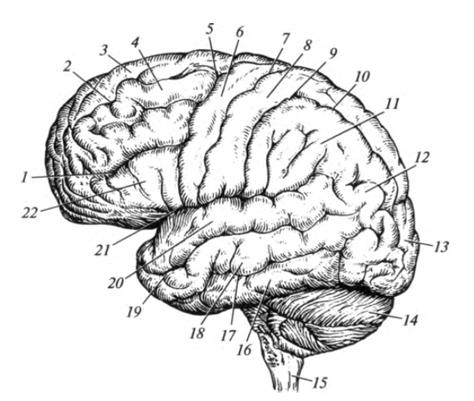

Анатомические снимки верхнелатеральной поверхности головного мозга